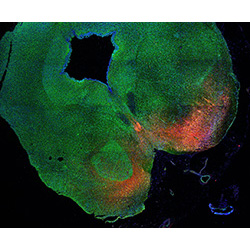

An anatomical analysis of the developing human midbrain from 6 post-conceptional weeks (PCW) to 22 PCW reveals increased tissue complexity, characterized by the emergence of dopaminergic nuclei, as highlighted by immunofluorescence analysis for tyrosine hydroxylase (TH).

12PCW

DAPI

13PCW human midbrain

GFAP

TH

Merged